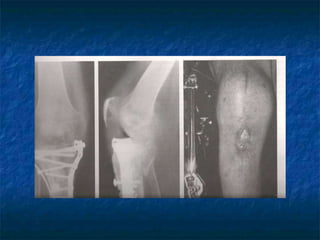

Fraturas expostas

 Raras;

 Desbridamento e irrigação abundante;

 ATB cefalosporina por 48hs;

 Avaliar as condições para fixação imediata.

Ferida da fratura deve permanecer aberta.

 Avaliar a fixação interna definitiva da

fratura, casos Gustillo I e II;

 Fixador externo após lavagem;